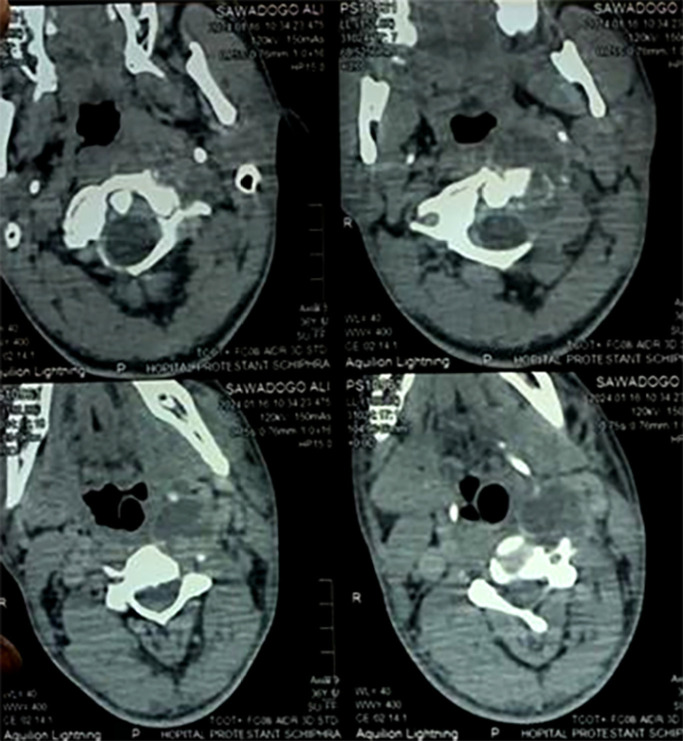

Observation: A 36-year-old black African patient of Burkinabè origin, with a history of tuberculosis infection (his mother had pulmonary tuberculosis) and no other pathological history, presented with chronic inflammatory cervicalgia that had been developing for six months in a non-febrile context of altered general condition. Examination showed a left latero-cervical swelling associated with a left basithoracic swelling, both fluctuant. Pleuropulmonary and neurological examinations were normal. HIV serology and tuberculin skin test were negative. Cervico-thoracic computed tomography revealed multiple abscesses. The abscesses were incised and drained. Analysis of the specimen showed the presence of acid-fast bacilli by direct examination and Mycobacterium tuberculosis by Xpert test, with sensitivity to rifampicine. The diagnosis was multiple tuberculous cold abscesses associated with cervical Pott's sore. The patient was started on standard analgesics and antituberculosis drugs for 12 months. The course was favorable, with a follow-up of one year after treatment.